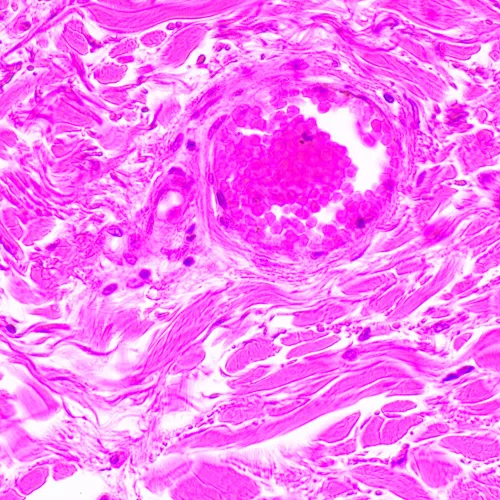

Изследователски клас микроскоп. Конструиран за наблюдение на прозрачни и полупрозрачни биологични проби, като например натривки и напречни сечения в преминаваща светлина по метода на светлото поле. Монтирането на допълнителни принадлежности ще осигури възможност за използване на методите на тъмното поле, фазовия контраст, диференциалния интерферентен контраст, флуоресценцията и поляризацията.

Микроскопът е подходящ за микробиологичен анализ, медицински диагностики и решаване на научни и изследователски проблеми.

Фазовоконтрастни устройства, флуоресцентно приспособление, кондензери за тъмно поле, устройства за поляризация и DIC устройства увеличават контрастните методи и позволяват изучаването на обекти, невидими в светлото поле.

- Наблюдение на прозрачни и полупрозрачни образци по метода на светлото поле с пропусната светлина